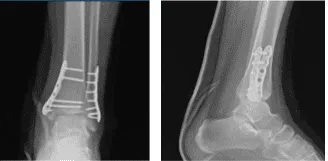

Para entonces, se aconsejó al paciente que realizara la Práctica R.I.C.E (Reposo, Hielo, Compresión y Elevación). Se revisó y monitorizó la radiografía del tobillo izquierdo durante 32 semanas postoperatoria, mostrando fracturas quirúrgicamente tratadas en el peroné distal y la maléola medial.

Radiografía del tobillo izquierdo completada 3 o más visitas 1 semana después de la operación